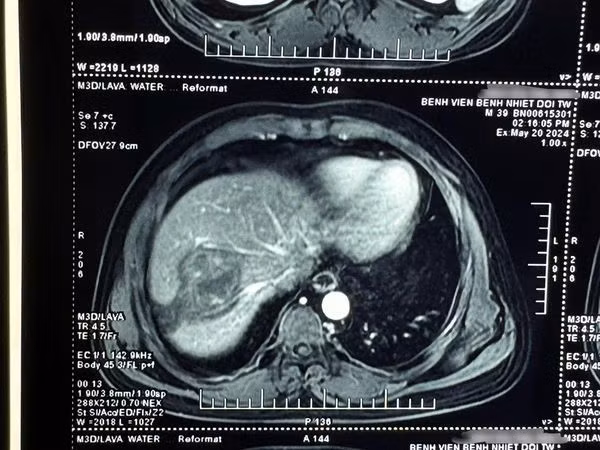

TS Vũ Minh Điền, phó Trưởng khoa Nội Tổng hợp, Bệnh viện Bệnh Nhiệt đới Trung ương cho biết: Qua thăm khám lâm sàng và khai thác tiền sử của bệnh nhân, chúng tôi đã nghĩ đến bệnh cảnh sán lá gan lớn khi các xét nghiệm ban đầu cho thấy có bạch cầu ái toan tăng cao và hình ảnh chụp phim cộng hưởng từ gan hướng nhiều đến bệnh sán lá gan lớn.

![]() |

| Ổ sán tạo thành u trên phim chụp - Ảnh BVCC |